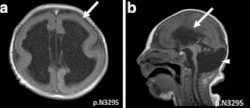

MRI of a patient with a TUBA1A mutation showing microlissencephaly with cerebellar hypoplasia. a. smooth brain surface (arrow) b. absent corpus callosum (arrow).